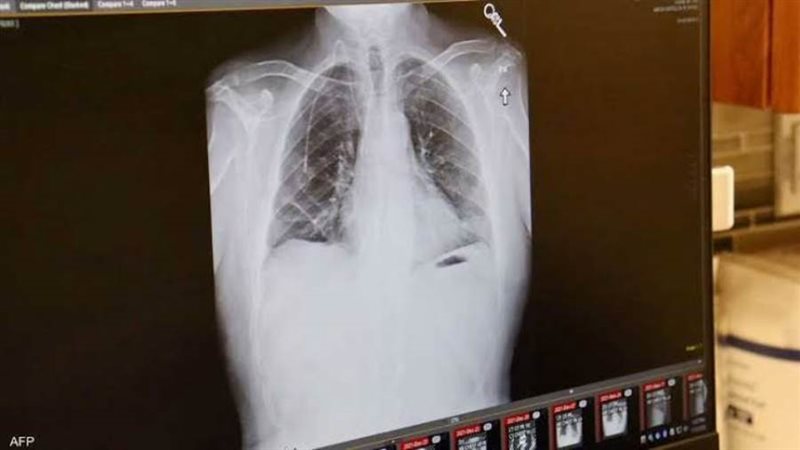

ويضيف أن سرطان الرئة، وخصوصا السرطان الغدي ( نوع من السرطان يبدأ في الغدد التي تفرز مواد مثل المخاط أو السوائل في أنسجة الجسم وقد يصيب الرئة)، لا تظهر أعراضه في المراحل الأولى، مثل السعال وألم الصدر وضيق التنفس، إلا عندما يكون الورم قد انتشر، ولهذا تشخص أغلب حالات هذا المرض في مرحلة متقدمة.

وأشار تقرير لـ"بي بي سي"، إلى أن نسبة الإصابة بسرطان الرئة تزداد كل سنة، وهو أكثر شيوعا بين النساء، خاصة من أصول آسيوية، معتبرا أن للهرمونات الأنثوية تأثيرا على ظهور هذا النوع من السرطان". وأوضح التقرير ذاته، أن من بين أسباب الإصابة بسرطان الرئة استنشاق الغازات، والتدخين غير المباشر، والتعرض لأبخرة الطهي، أو الوقود الصلب مثل الحطب والفحم في أماكن سيئة التهوية، وبما أن النساء يقضين وقتا أطول داخل المنازل، فإنهن أكثر عرضة لهذا النوع من التلوث الهوائي، وبالتالي أكثر عرضة للإصابة بسرطان الرئة. وكشفت الأبحاث أن تلوث الهواء الخارجي، هو ثاني سبب رئيسي لسرطان الرئة بعد التدخين، لا سيما بعوادم السيارات ومداخ المصانع والدخان الناجم عن حرق الفحم والخشب، ما يجعل الأشخاص الذين يعيشون في مناطق ملوثة هم أكثر عرضة للوفاة بسبب المرض. وفي عام 2022، قدرت الوكالة الدولية لأبحاث السرطان (IARC) أن 194,000 حالة سرطان رئة من نوع الغدة الرئوي حول العالم تعود إلى تلوث الهواء معظمها في شرق آسيا، خاصة في الصين، بينما تم تشخيص 1100 شخص بسرطان الغدة الرئوي في المملكة المتحدة بسبب تلوث الهواء.

وشهدت السنوات الأخيرة تحسنا كبيرا في تشخيص هذا المرض، حيث ارتفع متوسط البقاء على قيد الحياة لدى المرضى الخاضعين للعلاج إلى أكثر من عشر سنوات، بعدما كان لا يتجاوز سابقا سنة واحدة.